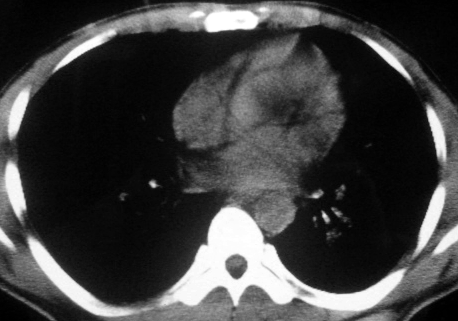

男,36岁,一月前醉酒淋雨后发热咳嗽,气短进行性加重.

抗生素治疗无效,痰检(一).

影像诊断:结核? 还有其他考虑吗?

双肺内中部见略不对称性蝶翼状高密度区,边界不清,部分呈磨玻璃样密度,并可见含气支气管征。肺门、纵隔内未见肿大淋巴结影。无胸腔积液。

考虑:1、肺炎,建议进一步查冷凝集试验除外支原体肺炎;

2、不除外霉菌感染。

双肺斑片状密度均匀病灶,边界模糊可见充气支气管征,上野多于下野,不支持结核,1肺内感染,2查肾功,中心型肺水肿待除外.

双肺中上野对称分布蝶翼样不均匀密度增高影,有支气管充气征,纵隔未见肿大淋巴结,发病突然,抗炎治疗无效,还是要考虑结核。

还是考虑肺水肿!蝶翼征.肺门增大,肺血管影增粗,!!病变累及中内带为主!要排外支原体感染.

支持: 双肺内中部见略不对称性蝶翼状高密度区,边界不清,部分呈磨玻璃样密度,并可见含气支气管征。肺门、纵隔内未见肿大淋巴结影。无胸腔积液。